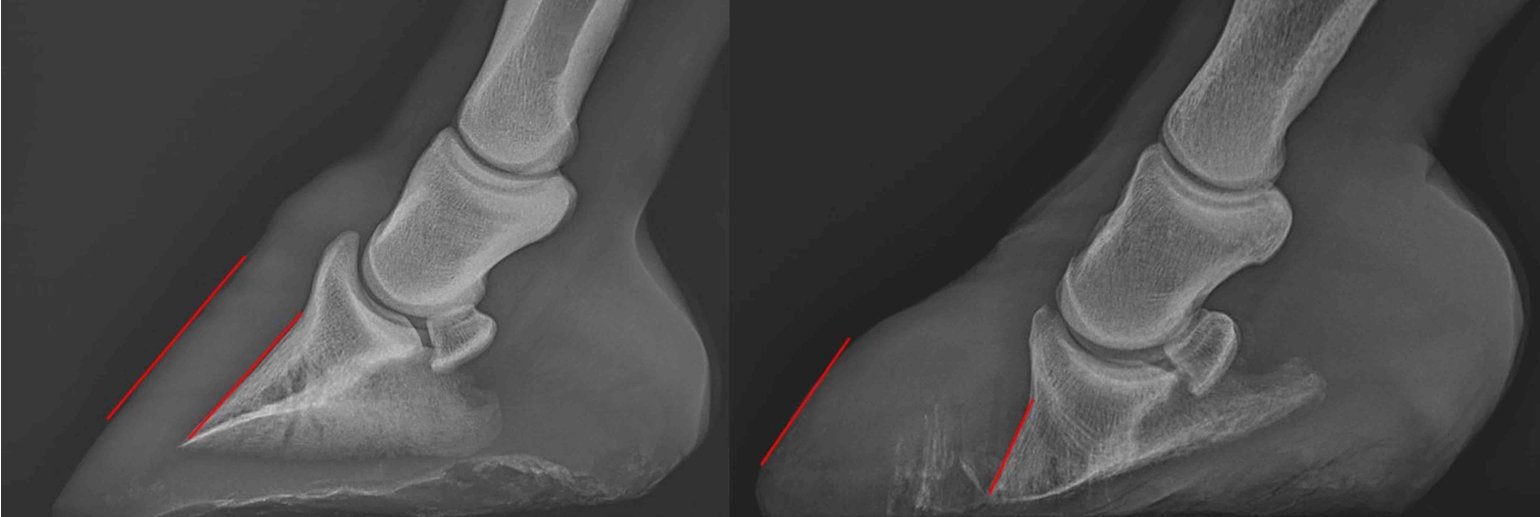

X-ray images of a healthy horse (left) and a laminitic horse (right)

Laminitis is incurable but it can be slowed down and managed. Aside from prevention, the most important thing in Laminitis management is early detection. “We don’t want it to get to a point where it is so bad that it is causing the horse visible discomfort. The most effective way for early detection is through X-ray imaging which detects very subtle changes in the angulation of the bone, so even if there is a slight rotation in the bone, indicating early onset of Laminitis, this can be seen in the X-ray.”

To create this reference, Dr. Johnson is taking X-ray measurements of the feet of over 100 healthy Arabians. Once the reference is created, there will be a better understanding of what is “normal” for an Arabian, and the reference will be used to detect very subtle changes in the bone angulation.